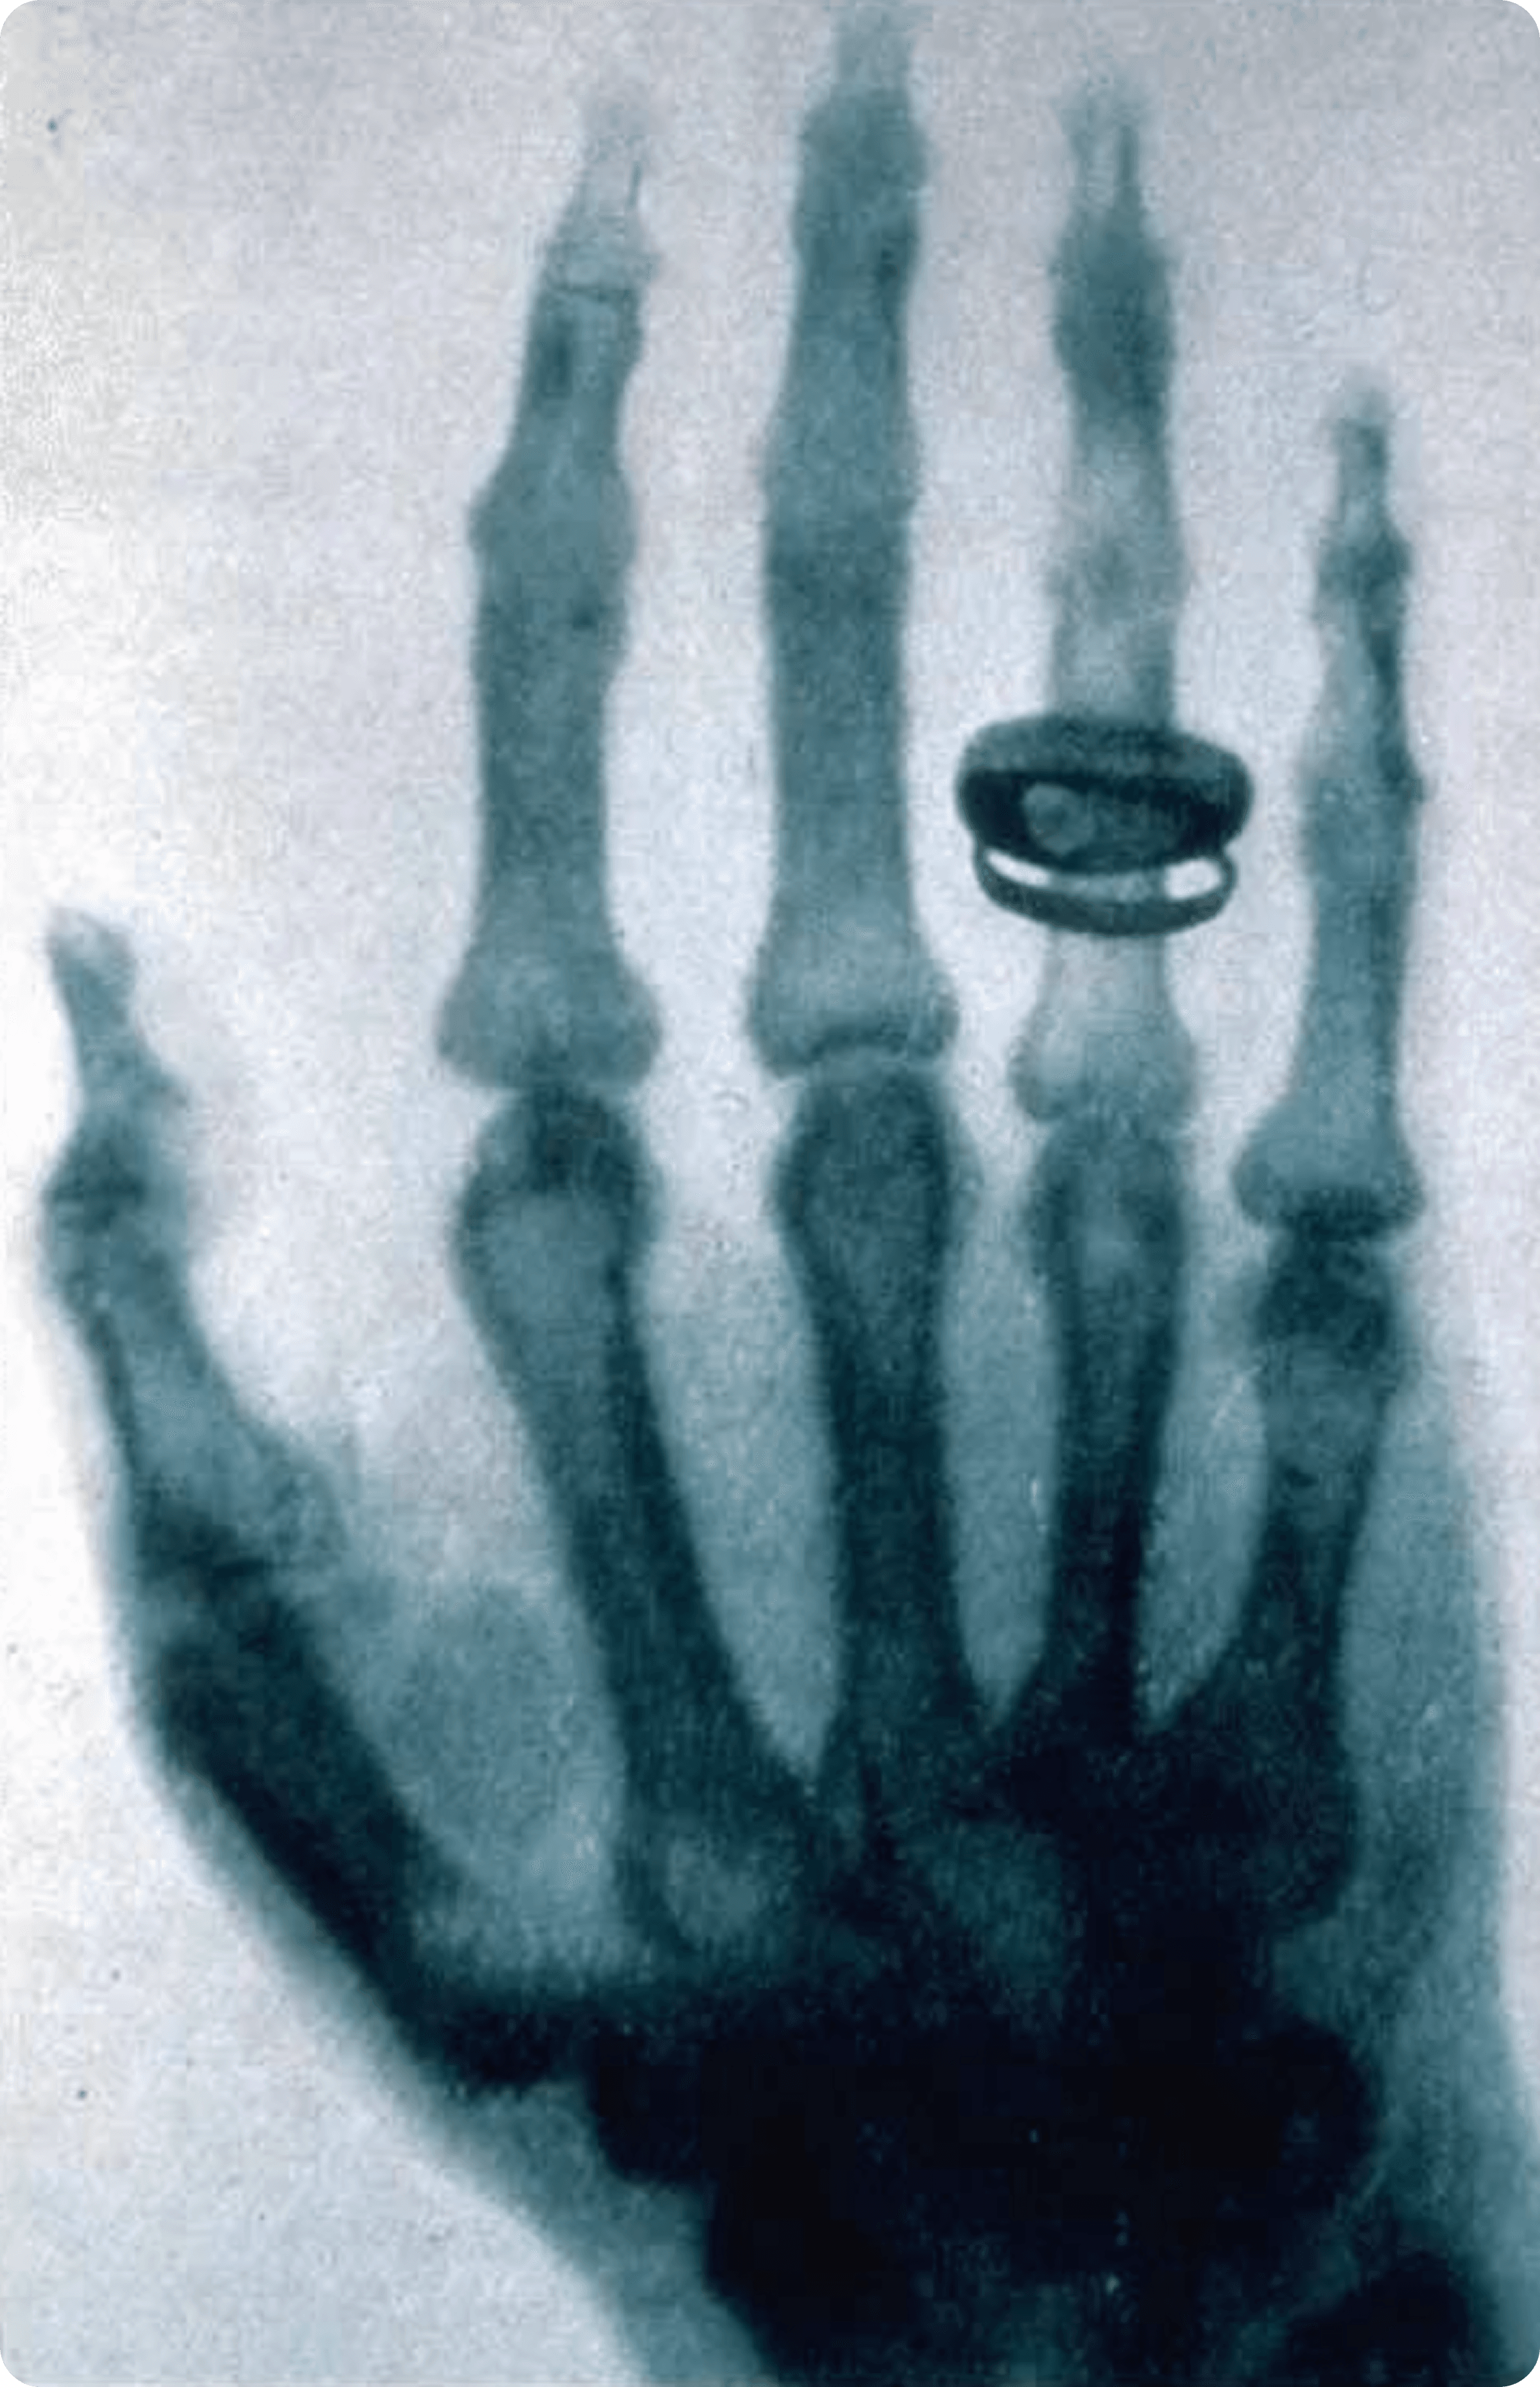

下图为人类首张 X 光照片:

在更多领域中,X 光图像具有一种独特的审美特征:物质不再以表象区分,而是以密度呈现;轮廓并非由线条勾勒,而是由吸收率的差异自然生成。半透明、层层叠加的影像,让物体失去重量感,却获得了一种冷静而诚实的秩序。这种视觉语言天然地剥离了装饰性,指向结构、关系与本质。